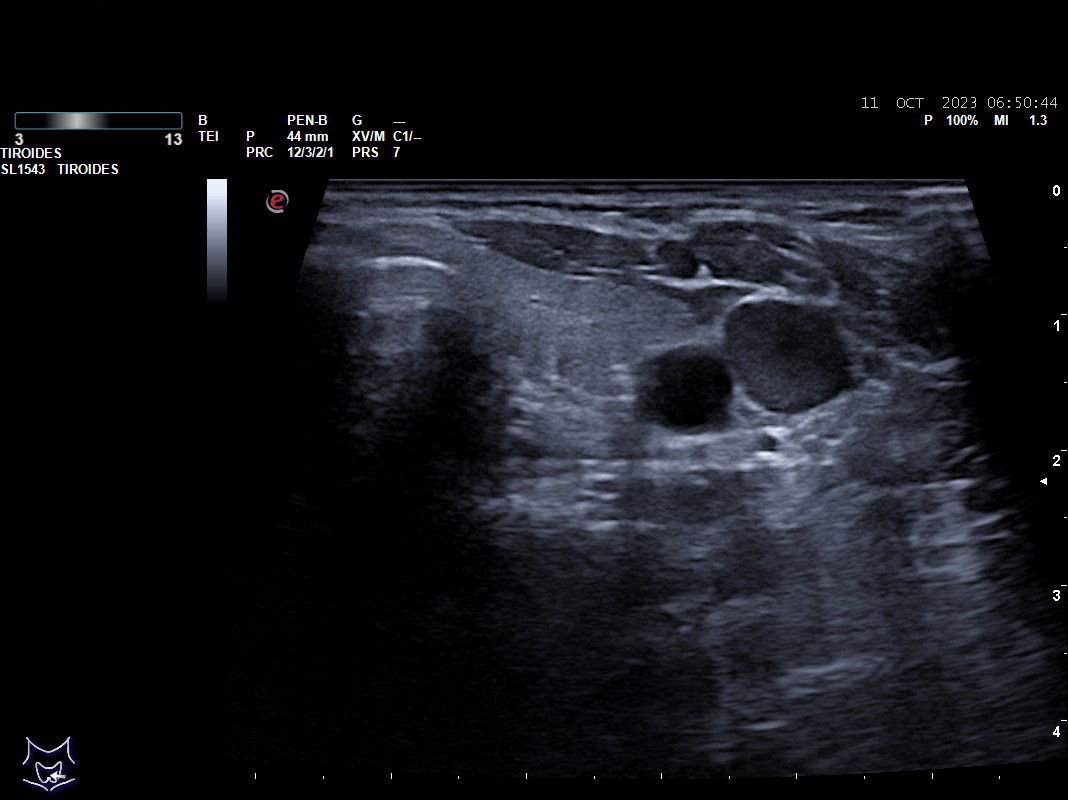

Hallazgos ecográficos: nódulos tiroideos subcentimétricos sin cambios, yugular interna izda con contenido discretamente hiperecogénico que no capta Doppler y colapsabilidad incompleta.

Desde hace un mes sensación de presión en región cervical anterior e inferior, exploración del cuello normal y se programa para una eco cervical.